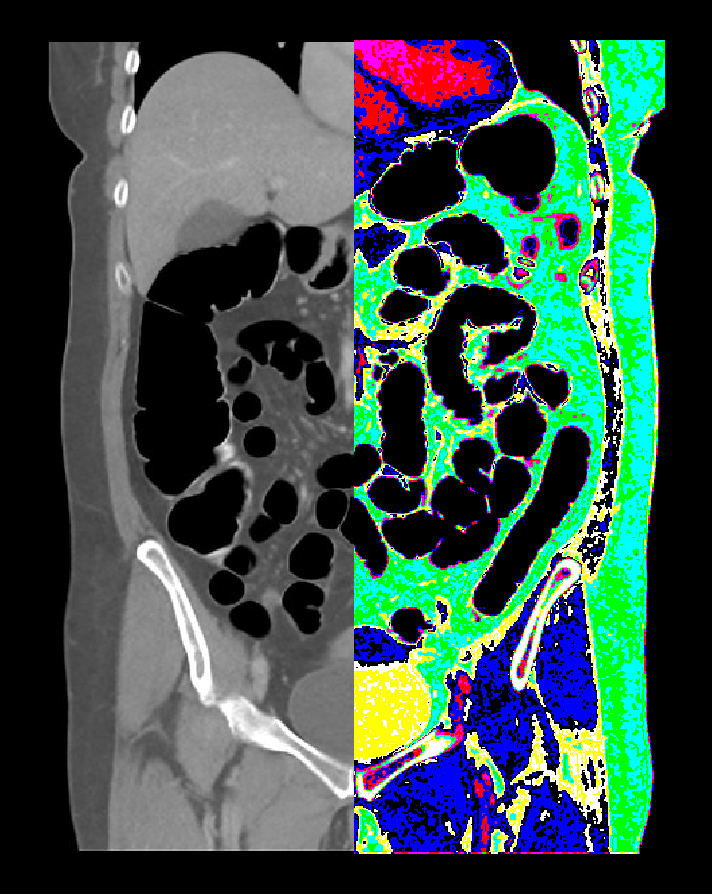

- Axial, coronal and sagittal images in soft-tissue window (WL 500, WW 50) with ≤ 5mm slicethickness can be generated.

- Axial, coronal and sagittal images in bone-window (WL 3500, WW 350) with ≤ 3mm slice thickness can be generated.